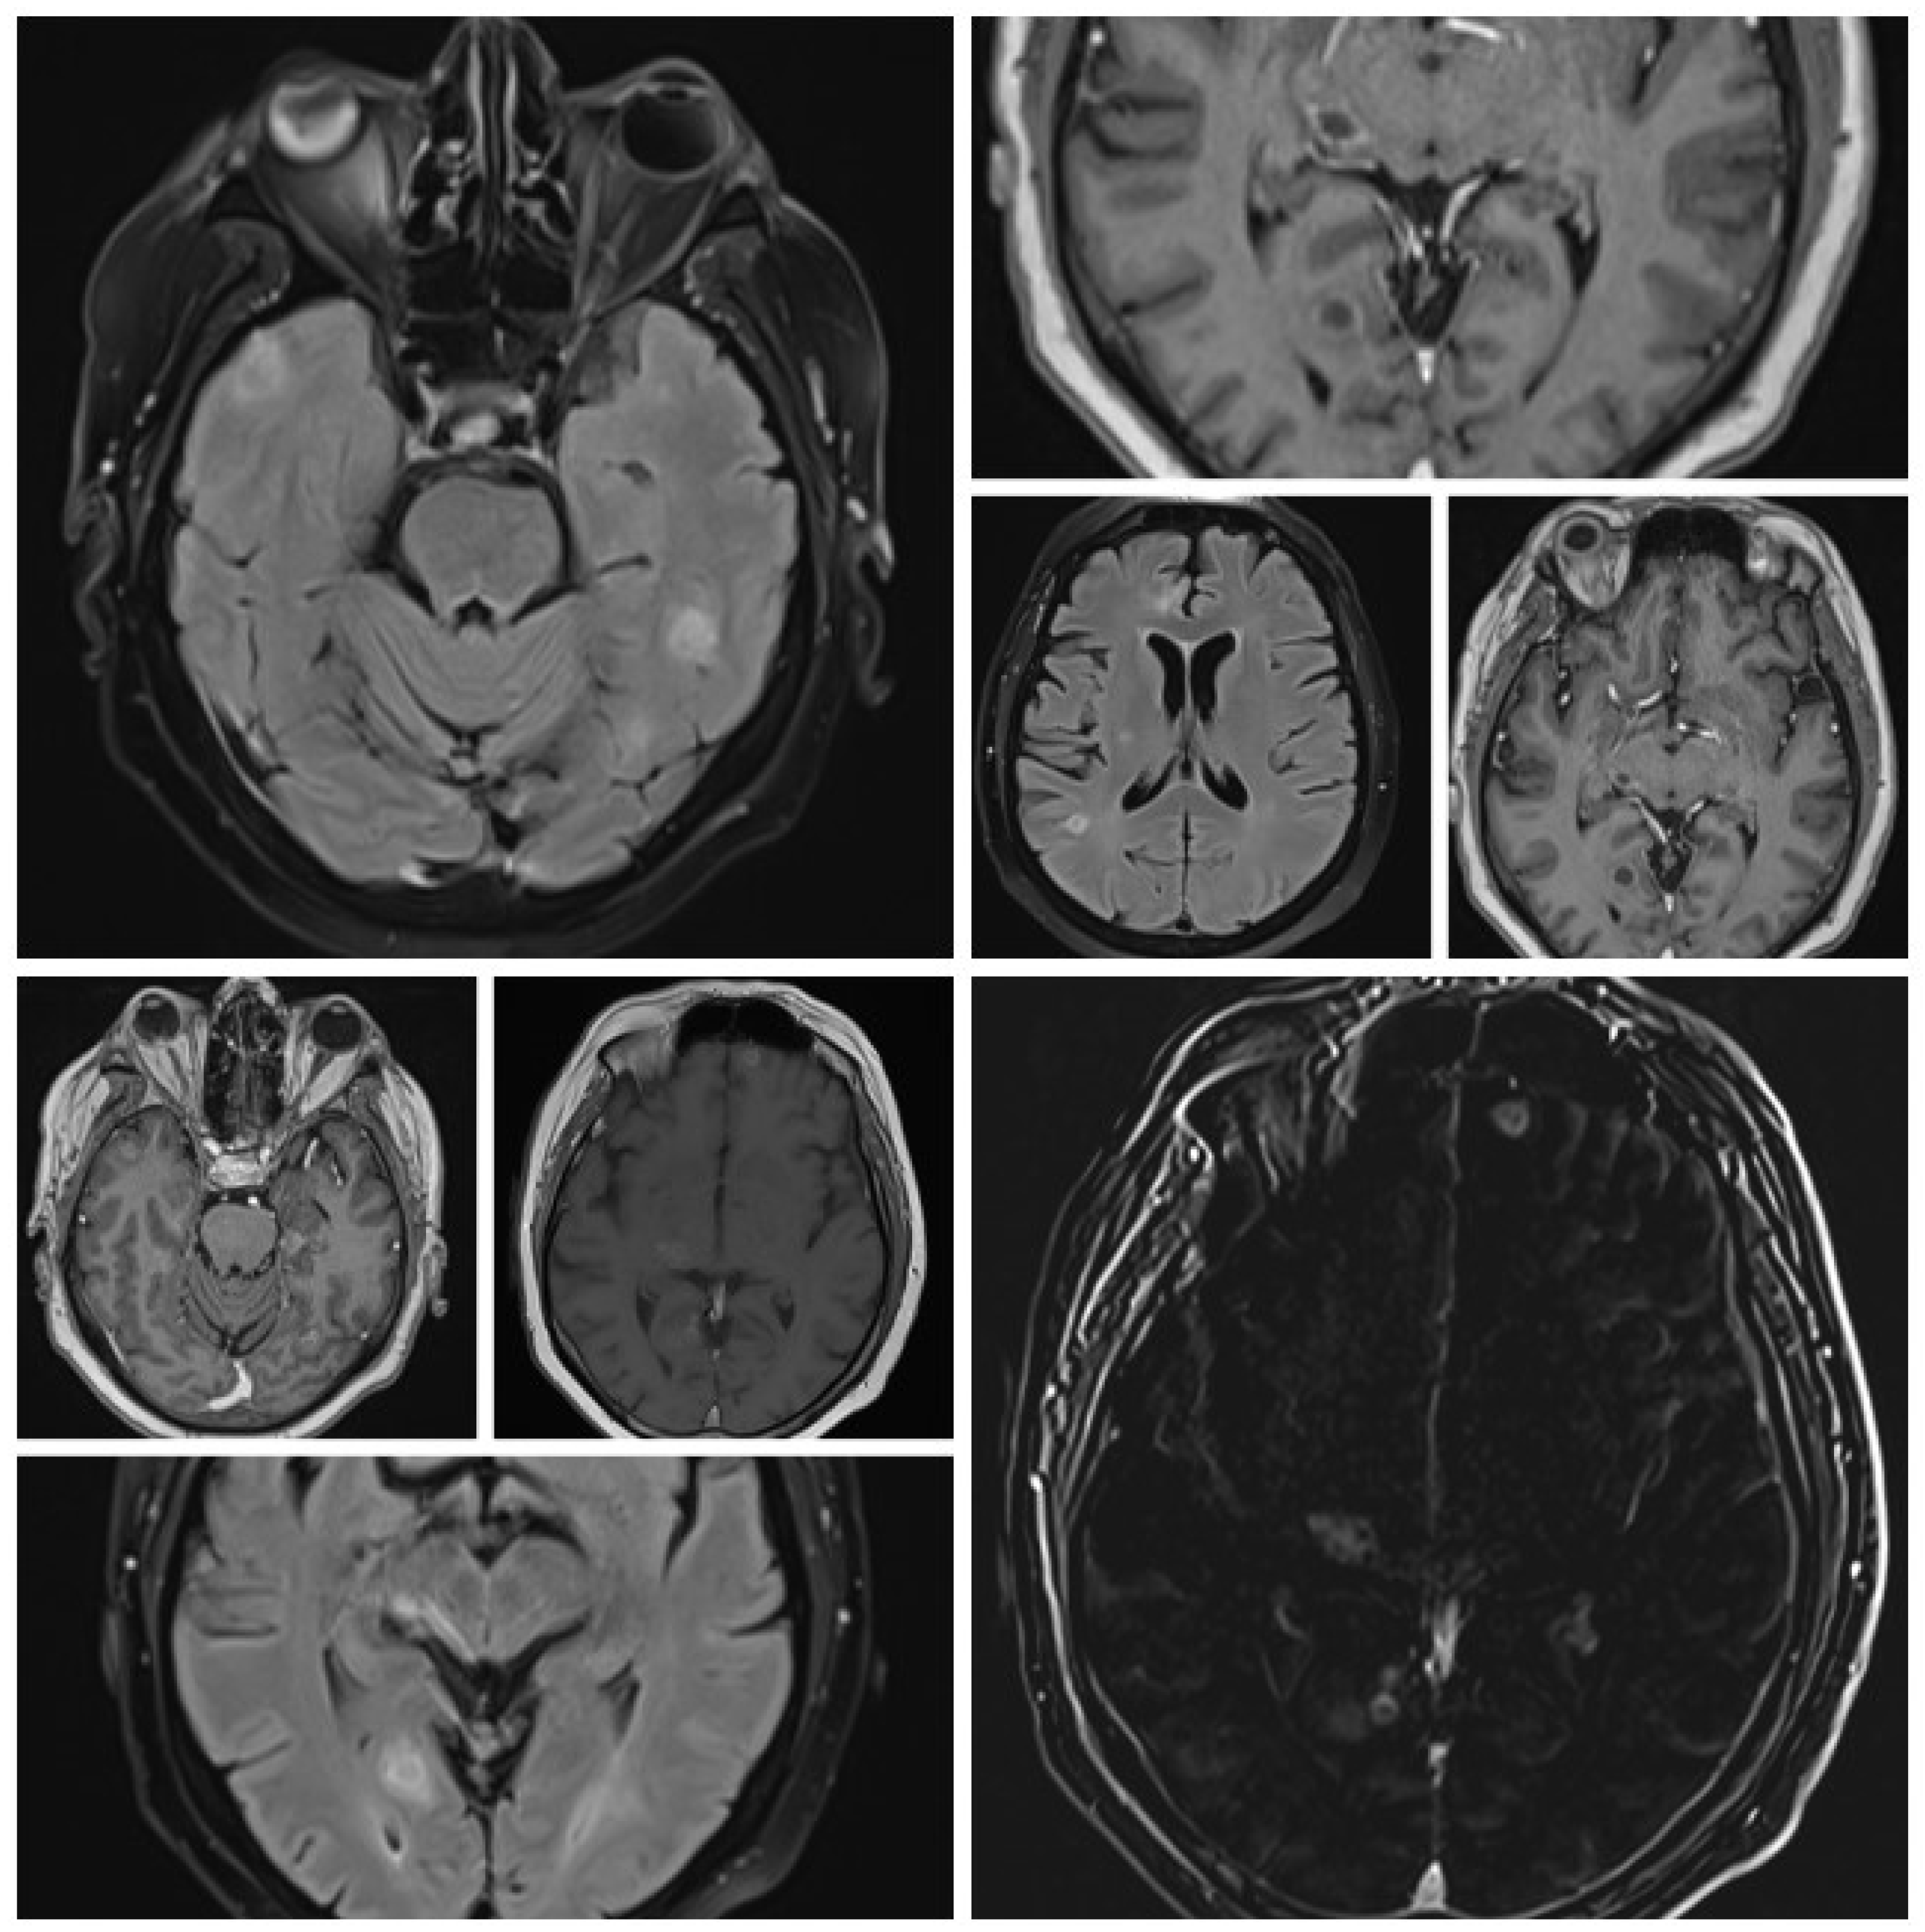

In early May 2023, the patient developed a respiratory illness that was treated with iv. gentamycin and ceftriaxone for 7 days in a territorial hospital and discharged. In late May 2023 he developed right retrorbital pain, painful right red eye with acute vision loss, headaches, 7 kg weight loss, and aggravated fatigue that were not controlled with usual medication and cough. The patient was admitted to the Internal Medicine Department for further evaluation. We performed a native cranial CT (Figure 1) and an MRI without contrast which showed multiple lesions -10- that were classified as undetermined lesions on CT scan and possible abscessed metastases on the MRI.

It was suspected that there was a metastatic tumor and a full-body CT scan was performed (Figure 2). The CT scan discovered multiple abscesses in the lungs and under the skin. A second contrast MRI (Figure 3) scan was conducted which revealed abscesses in all parts of the brain, including the right thalamus and left cerebellar hemisphere, with ring-like contrast-enhancing lesions. However, the lesions were relatively stable compared to the previous MRI.

Figure 1. Initial cranial CT (no contrast).

Figure 3. MRI (different sequences showing brain abscesses).